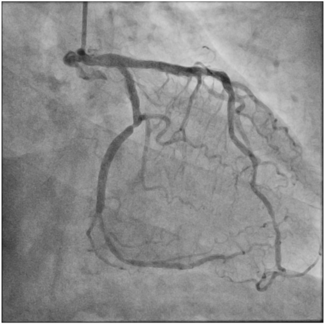

Tak-Shun Chung, MD, MBBS; Sui-Fung Wong, MBChB

A 71-year-old man who had undergone percutaneous transluminal coronary angioplasty in 2013 was admitted for unstable angina.

02/14/2024